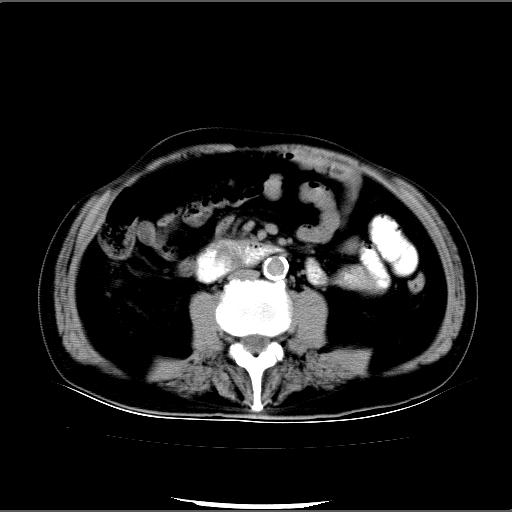

患者男82岁,黄染,发热10天,无腹痛。

1胆总管下端结石伴肝内外胆管扩张;2胆囊颈部结石伴胆囊积液

胆囊多发结石,胆囊积液;胆总管中下段结石,中上段扩张。

胆总管下段结石伴胆道系统扩张;胆囊炎伴胆囊结石.

有时胆总管下段结石的密度并不是均匀的高密度,而是以高密度为主的伴中心等密度的混合物,这与胆道结石的多样性有关,少数时候诊断困难时应结合临床病史,症状等,还有增强扫描都可以帮助明确诊断!!常与胆道蛔虫伴钙化鉴别!

顺便说说临床怀疑胆石症的病人ct检查前的肠道准备最好不要喝阳性对比剂!可以给予阴性对比剂,如水.这样可以避免干扰!

1、胆总管壶腹部结石并胆总管、胆囊及肝内胆管扩张。2、胆囊多发结石。3、两下胸膜局限性增厚。4、胃体部大弯侧胃壁稍厚,建议:多量饮水后增强ct扫描除外占位性病变。

十二指肠乳头旁憩室伴胆总管下段结石,胆囊结石

胆囊结石、胆总管下端结石,胆囊积液扩大。另外胃壁增厚胃腔缩小,应进一步检查排除皮革胃。

此病例有结果了:患者术后为:胆总管下段结石伴胆道系统扩张;胆囊炎伴胆囊结石。

各位战友分析的都很正确,是一个典型的病例。